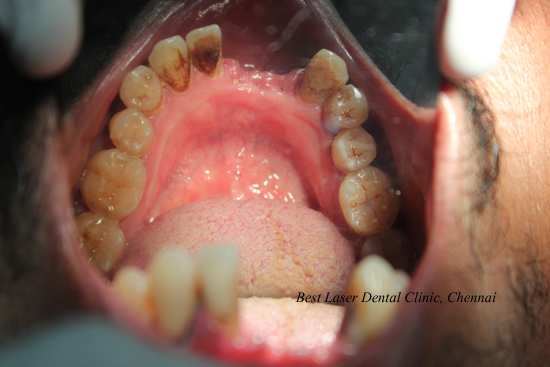

Lower Front Tooth Replacement using dental implants